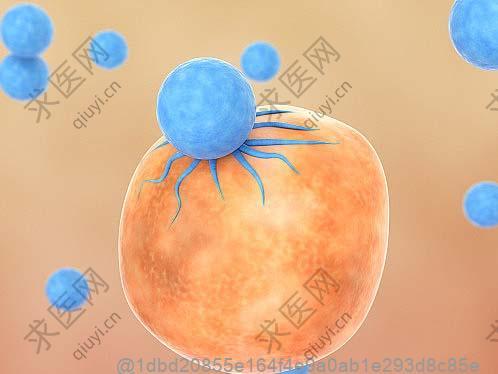

干细胞治疗这种被视作先进医疗手段的方法,其目的是助力受损细胞进行修复或替换,而在完成干细胞治疗之后,饮食方面的恰当调整对身体恢复所起到的重要作用不容忽视。螃蟹属于富含丰富蛋白质、维生素以及微量元素且对健康有益的海鲜类别,但关于接受干细胞治疗后食用螃蟹的适宜时间,却需要考虑诸多因素。

首先,在干细胞治疗后的初期阶段,由于身体可能处于极为敏感的状态,所以此时应当尽量避免食用像海鲜这类容易引发过敏反应的食物,这是鉴于部分人可能对海鲜存在过敏现象,并且干细胞治疗后人体的免疫系统或许会变得更加敏感。因此在干细胞治疗后的最初几天直至几周内(具体时长需依据个人体质以及医生所给出的建议为准),暂时避开食用螃蟹等海鲜类产品,以防引发不必要的健康问题。

干细胞(stem cells, SC)是一类具有自我复制能力(self-renewing)及多向分化潜能的细胞,在一定条件下,它可以分化成多种功能细胞。